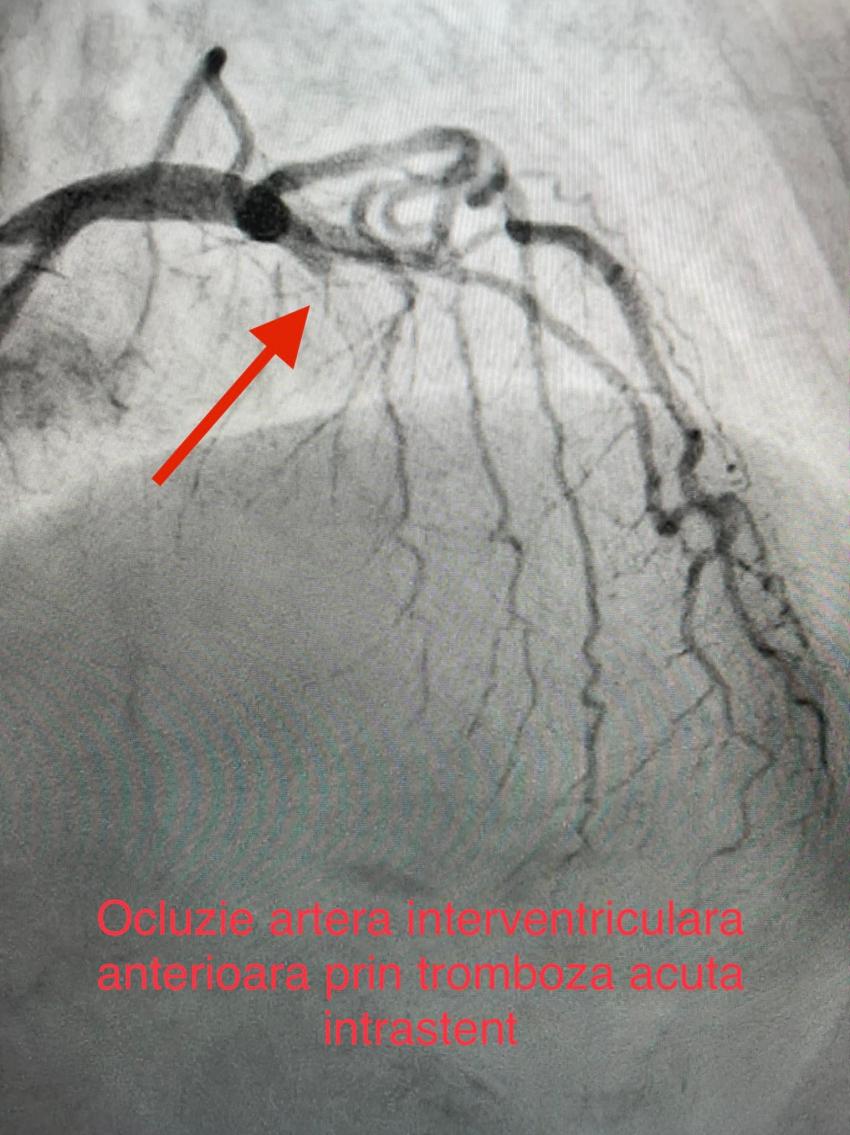

Pacienta a fost resuscitată, iar imediat echipa medicală a efectuat o coronarografie și a intrat în operație pentru realizarea mai multor proceduri de cardiologie intervențională.